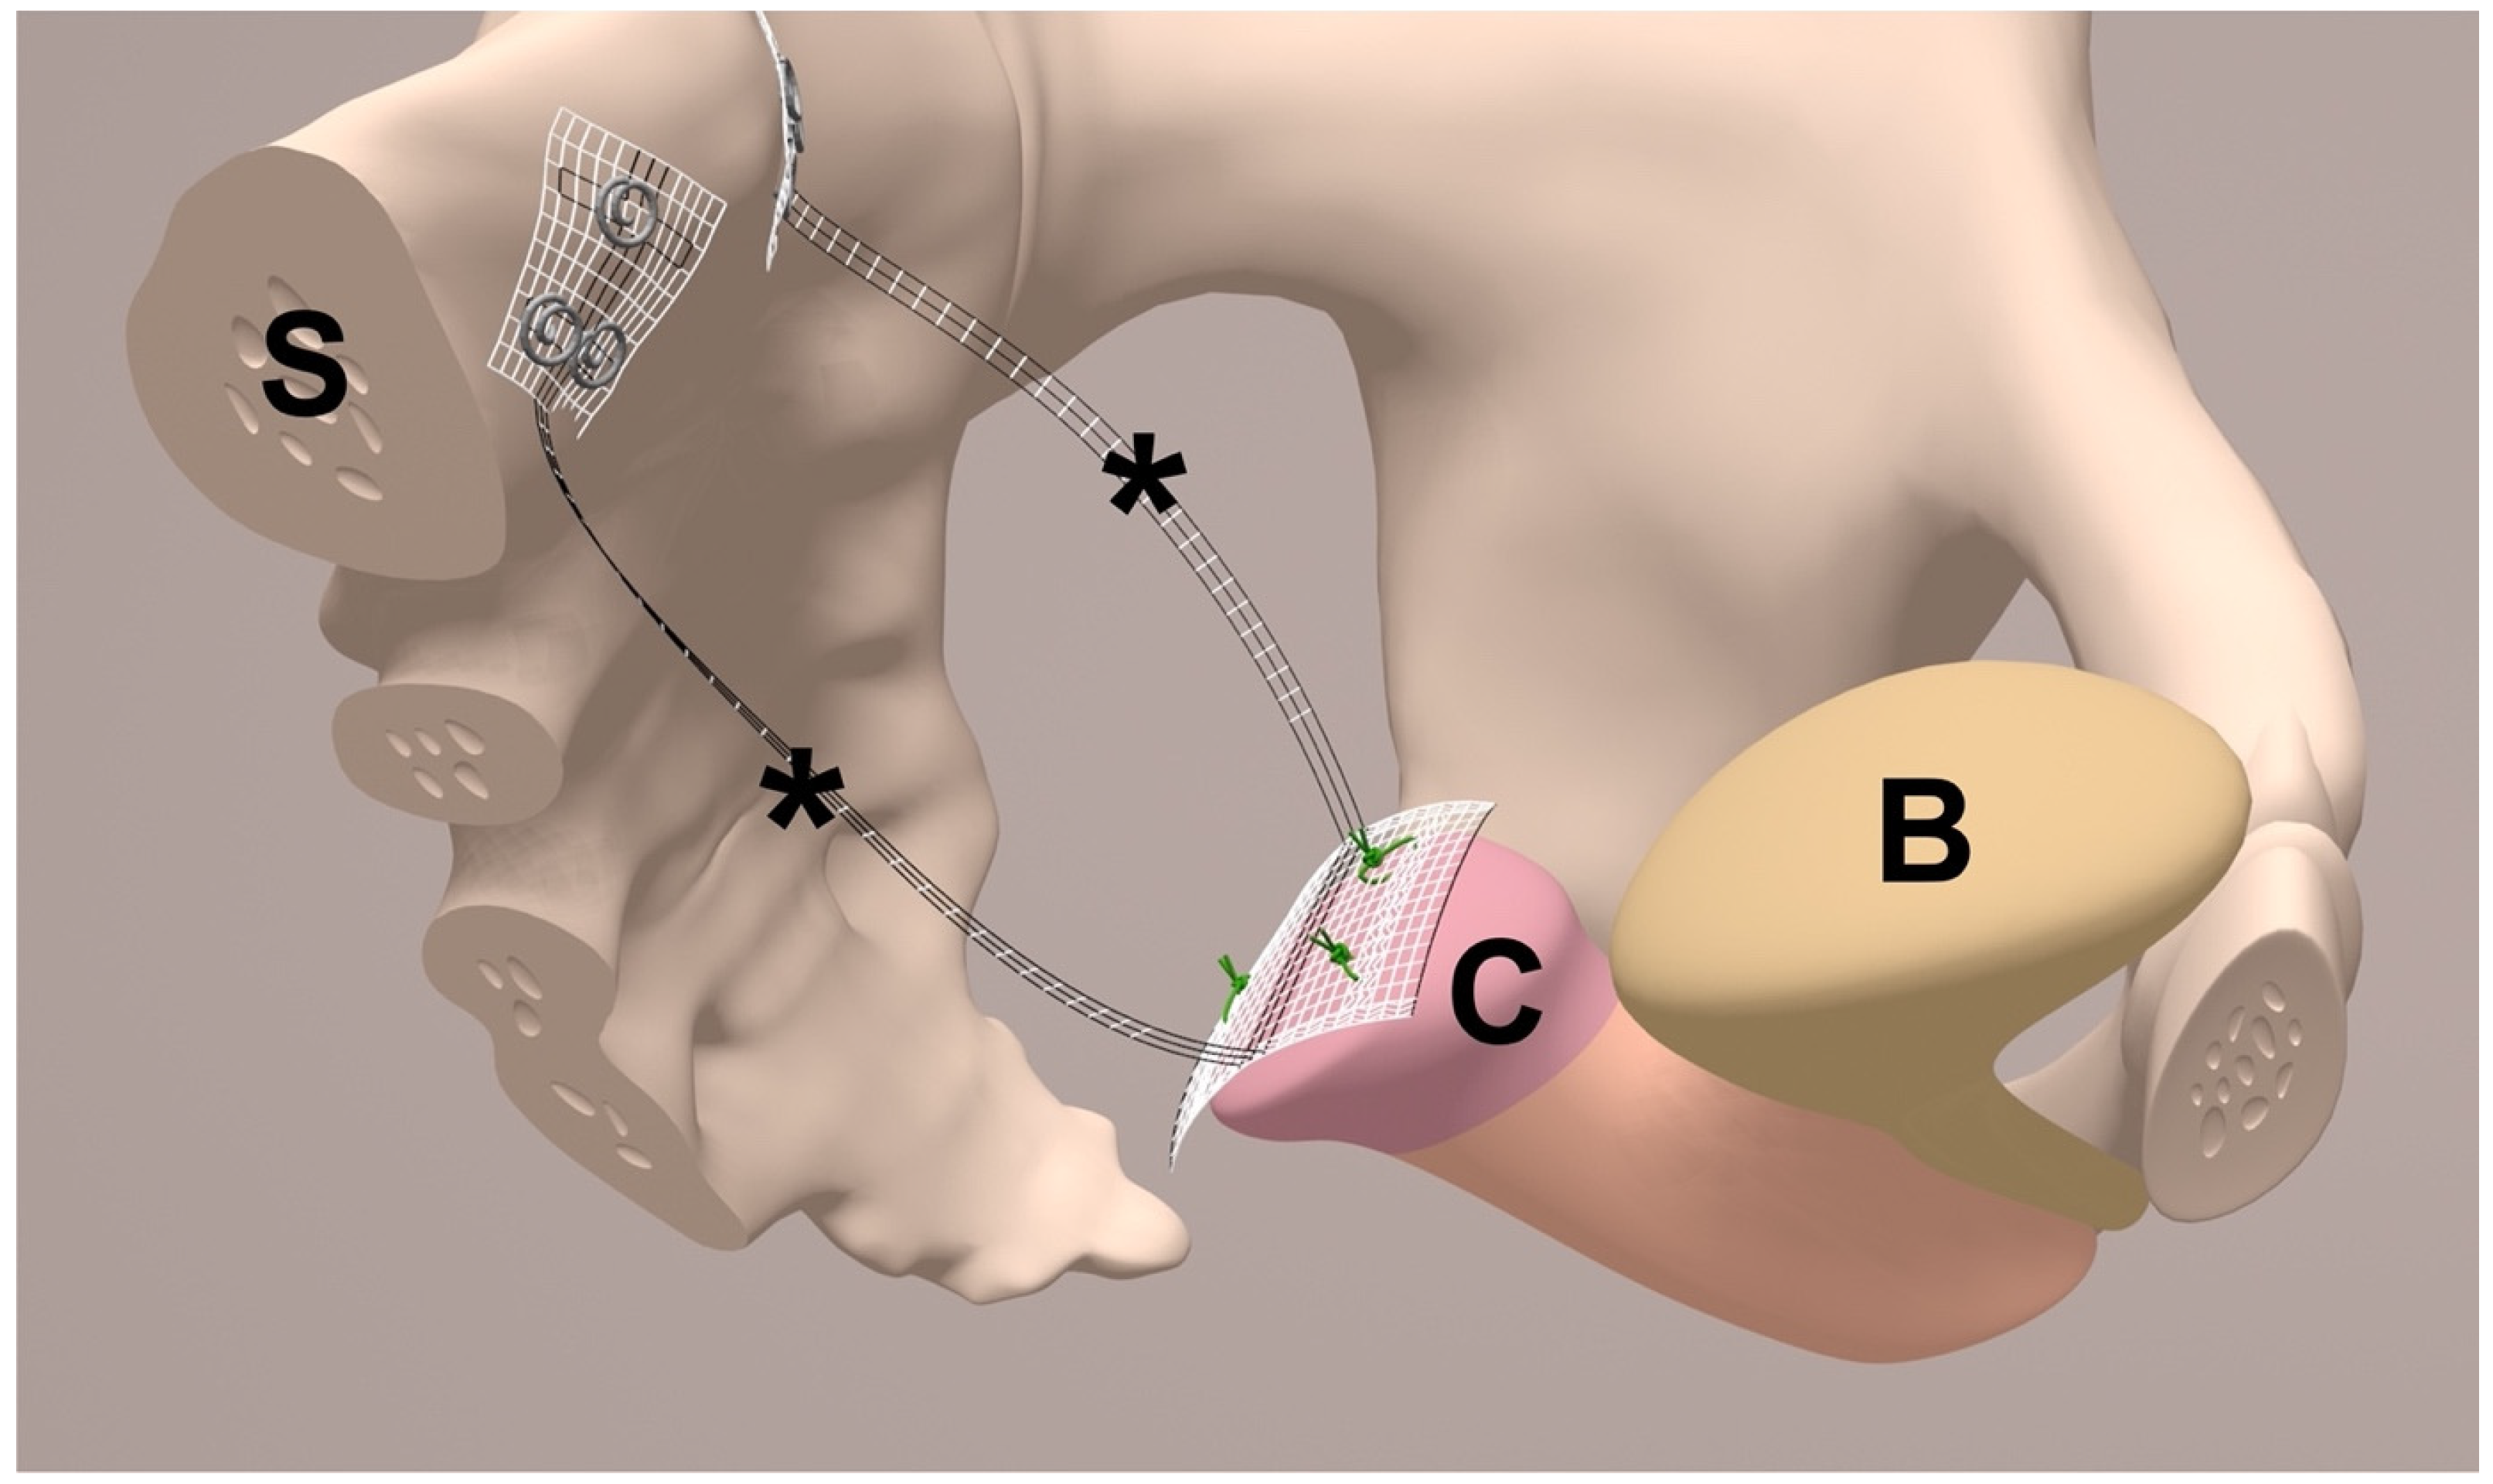

| Anterior fixation of middle part of PVDF structure e (Figure 1) | Sutured to the cut surface of the cervix with 4 interrupted, non-absorbable sutures f. | Sutured to the cut surface of the cervix with 3 interrupted, non-absorbable sutures f (Figure 8a). |

| Posterior fixation of left and right arm of PVDF structure (Figure 1) | At left and right prevertebral fascial layer at S1 with 2 interrupted, non-absorbable sutures each e within the defined locations at the PVDF structure. | At left and right prevertebral fascial layer on S1/promontory with 3 titanium helices each g within the defined locations at the PVDF structure (Figure 2 and Figure 7). |